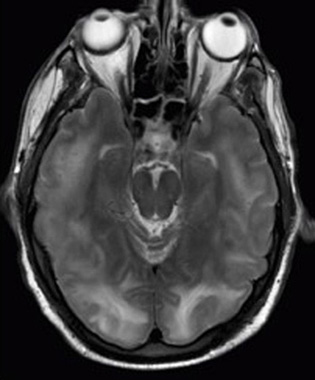

These two applications of physics have more in common than meets the eye. Microwave ovens use electromagnetic waves to heat food. Magnetic resonance imaging (MRI) also uses electromagnetic waves to yield an image of the brain, from which the exact location of tumors can be determined. Image Attribution: Rashmi Chawla, Daniel Smith, and Paul E. Marik

On the macroscopic level, it can explain the heat, work, and power associated with the human body. Physics is involved in medical diagnostics, such as x-rays, magnetic resonance imaging (MRI), and ultrasonic blood flow measurements. Medical therapy sometimes directly involves physics. For example, cancer radiotherapy uses ionizing radiation. Physics can also explain sensory phenomena, such as how musical instruments make sound, how the eye detects color, and how lasers can transmit information.